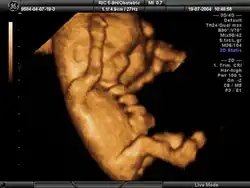

Ecografía obstétrica

La ecografía obstétrica[1]es un procedimiento de carácter médico usado para determinar la existencia de un embarazo y conocer las condiciones del embrión o feto, así como de la placenta, útero, cuello del útero y líquido amniótico. La ecografía es un procedimiento de diagnóstico que emplea el ultrasonido compuesto para crear imágenes bidimensionales o tridimensionales. Un pequeño instrumento (muy similar a un micrófono) llamado transductor emite ondas de ultrasonidos. Estas ondas sonoras de alta frecuencia se transmiten hacia la parte del cuerpo en cuestión (en este caso, el vientre) y se recibe su eco, el cual es procesado por un ordenador que muestra una imagen del feto sobre el que ha incidido el ultrasonido.

Esta técnica se considera el método más seguro para conocer el estado general del embarazo y, según las semanas de gestación, tiene sus indicaciones específicas. El examen se lleva a cabo a través de imágenes. Las ondas sonoras reflejadas en el interior del vientre materno permiten ver el desarrollo del feto. También se usa para ver los órganos pélvicos de la madre durante el embarazo. La ecografía obstétrica no emplea radiación ionizante.

Antes de realizar la ecografía, se recomienda que la madre beba dos o tres vasos de agua una hora antes de la prueba, para llenar la vejiga y así obtener una mejor imagen. La madre permanecerá acostada durante el procedimiento, mientras el ecografista aplicará un gel a base de agua en el abdomen, vientre y pubis. Este gel permitirá que las ondas sonoras enviadas por la sonda manual sean transmitidas al interior del abdomen materno. Estas ondas rebotarán sobre el feto o embrión, para producir una imagen en el ecógrafo. La imagen obtenida permitirá evaluar el estado de la gestación y el desarrollo del embrión o feto.